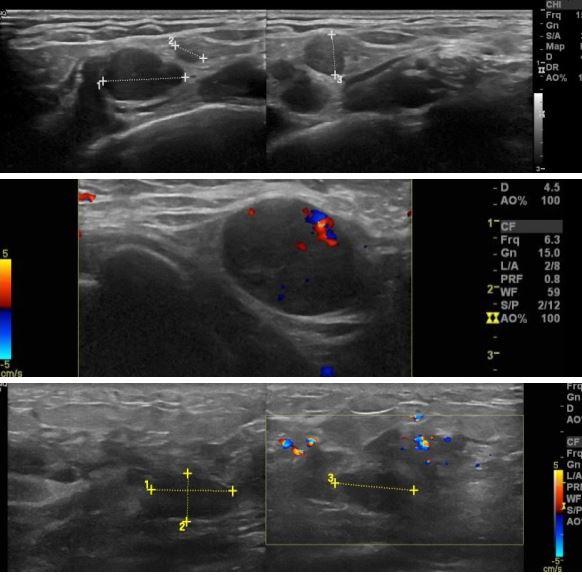

한달전에 좌측유방에 멍우리발견된후, 점점 커지는 느낌이고 유두함몰 진행되어

내원하신 30대 여자분으로 본원에서 좌측유방조직검사, 좌측 겨드랑이 조직검사,

좌측내유임파절 세포검사시행한 후 왼쪽유방 침윤성 아포크린유관암 진단되셨습니다.